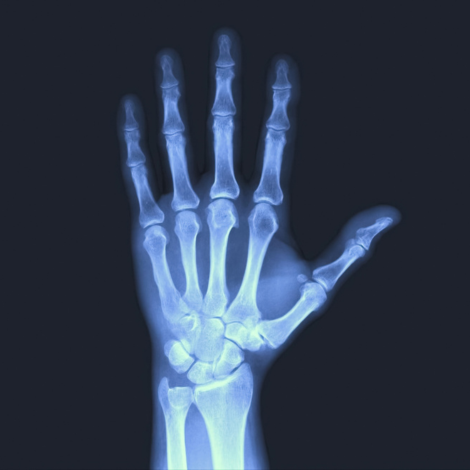

Wrist X-ray

Your healthcare provider uses a wrist X-ray to find the cause of any pain, swelling or tenderness in your wrist. They can use a wrist X-ray to diagnose possible health conditions involving your wrists. These conditions include: Broken bones (fractures) in your wrist; dislocated joints; degenerative conditions such as arthritis in your wrists.